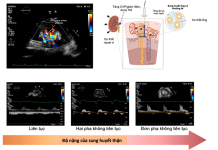

Quan điểm mới về đánh giá áp lực đổ đầy và quá tải dịch...

BS. NGUYỄN THANH HIỀN

BS. NGUYỄN TRẦN THU THỦY

1. GIỚI THIỆU

Sung huyết trong suy tim (ST) theo truyền thống được coi là một khái...